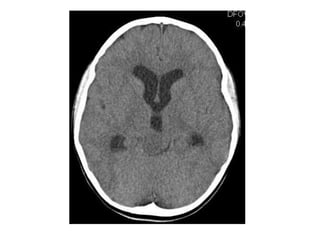

Axial nonenhanced CT shows a large pineal region mass with resultant hydrocephalus ,

the pineal calcifications are exploded toward the periphery (arrows)